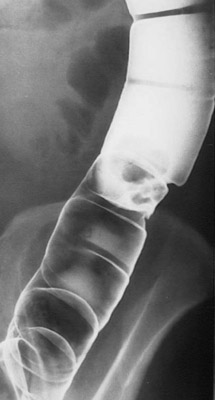

This barium enema reveals a polyp located midway down the descending colon. The polyp appears to be attached via a short stalk to the mucosa.